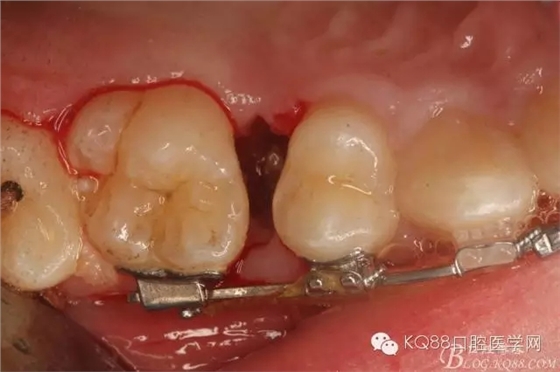

圖11.仔細(xì)考慮之后,在14頰側(cè)做垂直切口,切口長(zhǎng)度僅達(dá)膜齦聯(lián)合處,做小切口。

圖12. 做垂直切口+齦溝內(nèi)切口,形成角形瓣,暴露出15根面。